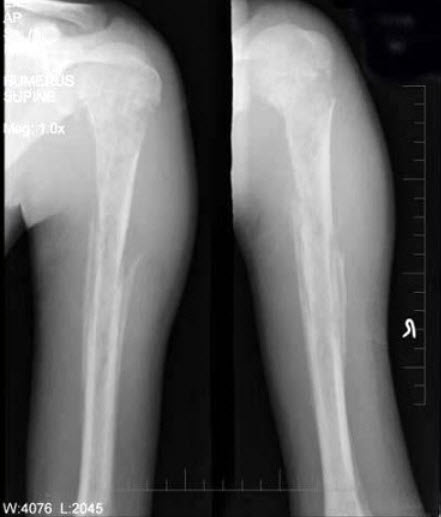

63、单项选择题

男,28岁,右上臂肿胀、疼痛,结合图像,最可能的诊断是()

A.骨肉瘤

B.成骨性骨转移瘤

C.化脓性骨髓炎

D.滑膜肉瘤

E.骨巨细胞瘤